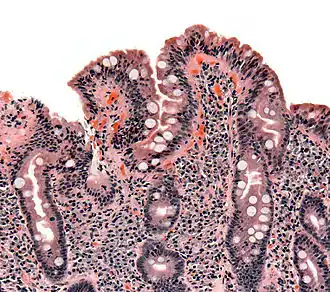

De vertering begint in de mond, waar het voedsel door kauwen wordt verkleind. Vervolgens wordt het in de maag en de dunne darm fijn gemaakt. De eigenlijke vertering geschiedt in de darmen met behulp van enzymen, die afkomstig zijn uit de maagwand, de alvleesklier en de darmwand. Ook gal uit de lever speelt een rol. De eindproducten worden ten slotte opgenomen via de darmvlokken van de darmen.

- Duodenoscopie (endoscopie van slokdarm, maag en twaalfvingerige darm) met biopten kan coeliakie, tropische spruw, ziekte van Whipple en andere aantonen.